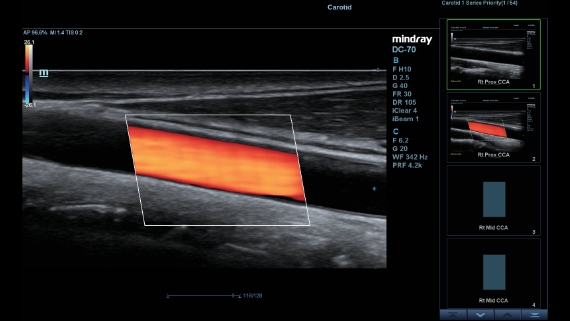

Als allround partner zet DC-60 Exp met X-Insight zich in om een allesomvattende oplossing te zoeken waarmee u alle aspecten van uw dagelijkse klinische activiteiten gemakkelijk en trefzeker kunt beheren.

De DC-60 Exp met X-Insight is ontworpen op basis van diepgaand inzicht in klantbehoeften om hoge effici?ntie met nauwkeurige beeldverwerking te leveren, dankzij eXacte helderheid, eXceptionele intelligentie en eXcellente ervaring.